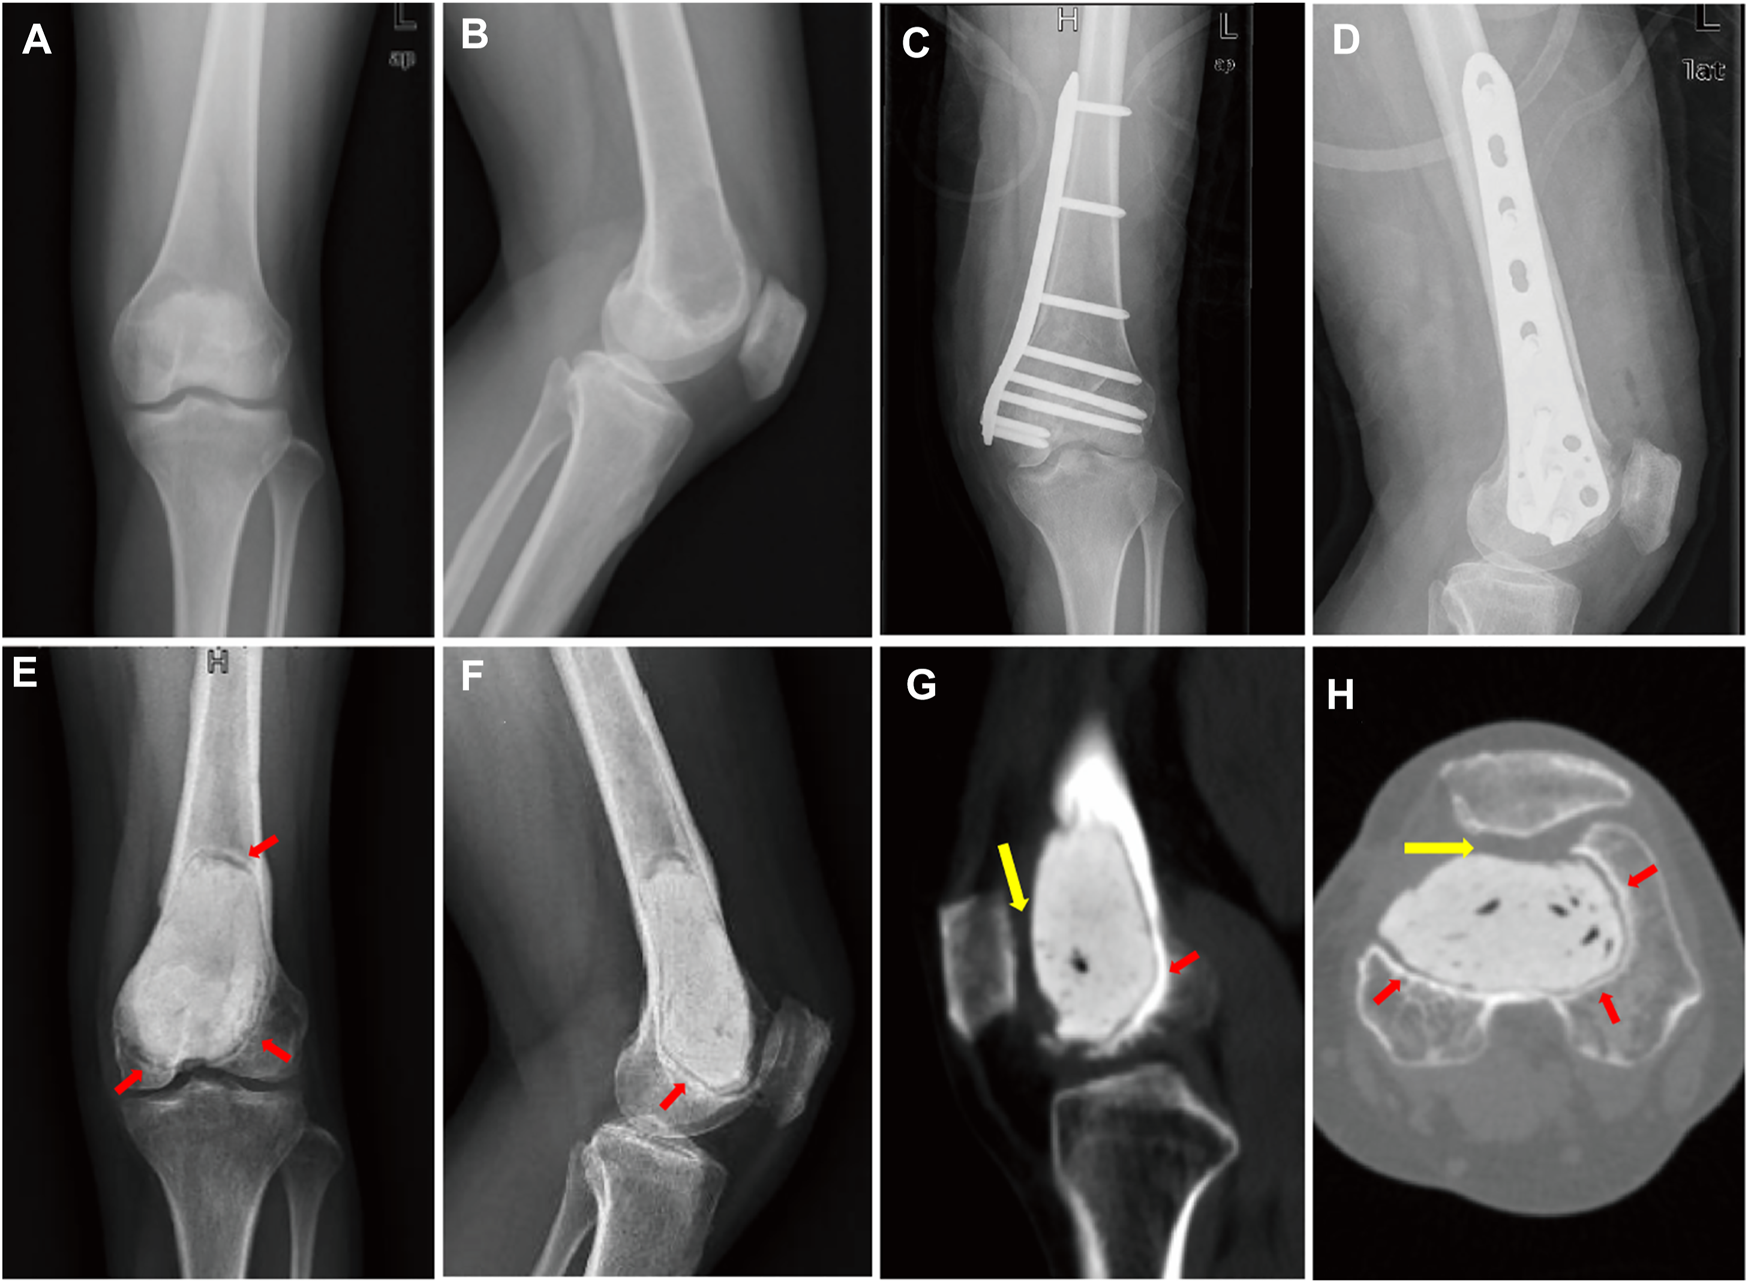

A 44-year-old female patient with progressive swelling and pain in the left knee for 4 months was admitted to West China Hospital in July 2018. X-ray images showed a large radiolucent area of bone caused by osteolytic deconstruction in the epiphyseal part of the left distal femur (Figures 1A,B). Computed tomography (CT), magnetic resonance imaging, emission computed tomography, and pathological biopsy were performed, and the patient was diagnosed with Campanacci Grade II GCT. In August 2018, the patient underwent intralesional curettage combined with autografting and internal fixation (Figures 1C,D). There were complications of deep infection 7 days after surgery and wound dressing change, and intravenous antibiotics were ineffective. Then, wound debridement and removal of internal fixation were performed. After the infection was controlled, the patient underwent cement packing. Afterwards, the pain persisted in the affected knee for 11 months (Figures 1E–H), and bone cement removal plus 3D-printed modular prosthesis reconstruction for patello-femoral large osteochondral defects was performed at our hospital on 15 August 2019. Pain and knee joint function were evaluated according to the Visual Analogue Scale (VAS), Rang of Motion (ROM), and Musculoskeletal Tumour Society (MSTS) scores. The VAS and MSTS scores were 7 and 15/30, respectively, before surgery. Knee flexion was 50°, and knee extension was normal before surgery.

FIGURE 1

(A) Anterior–posterior and (B) lateral X-ray images show a large radiolucent area in the epiphyseal part of the left distal femur. (C) Anterior–posterior and (D) lateral X-ray images after intralesional curettage combined autografting and internal fixation. (E) Anterior–posterior and (F) lateral X-ray images. (G) sagittal and (H) transverse planes on CT images after cement packing at 11 months. Sclerotic rim occurs around cement (red arrow). (G,H) Distal femur articular cartilage defects mainly lie in the patello-femoral joint (yellow arrow).